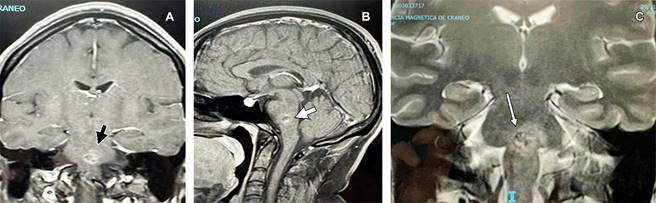

Dos años después, imágenes de resonancia magnética de cráneo ponderadas en T1 en cortes corona y sagital respectivamente (A y B) y, ponderada en T2 en corte coronal (C). Se muestra imagen en “palomita de maíz” (popcorn en idioma inglés), rodeada de halo difuso indicando edema y hemosiderina por sangrado de cavernoma en parte central de protuberancia.

Figura 2: